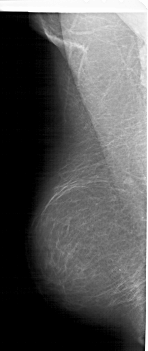

A_1422_1.LEFT_MLO

LEFT_MLO LINES 5956 PIXELS_PER_LINE 2506 BITS_PER_PIXEL 12 RESOLUTION 43.5 NON_OVERLAY